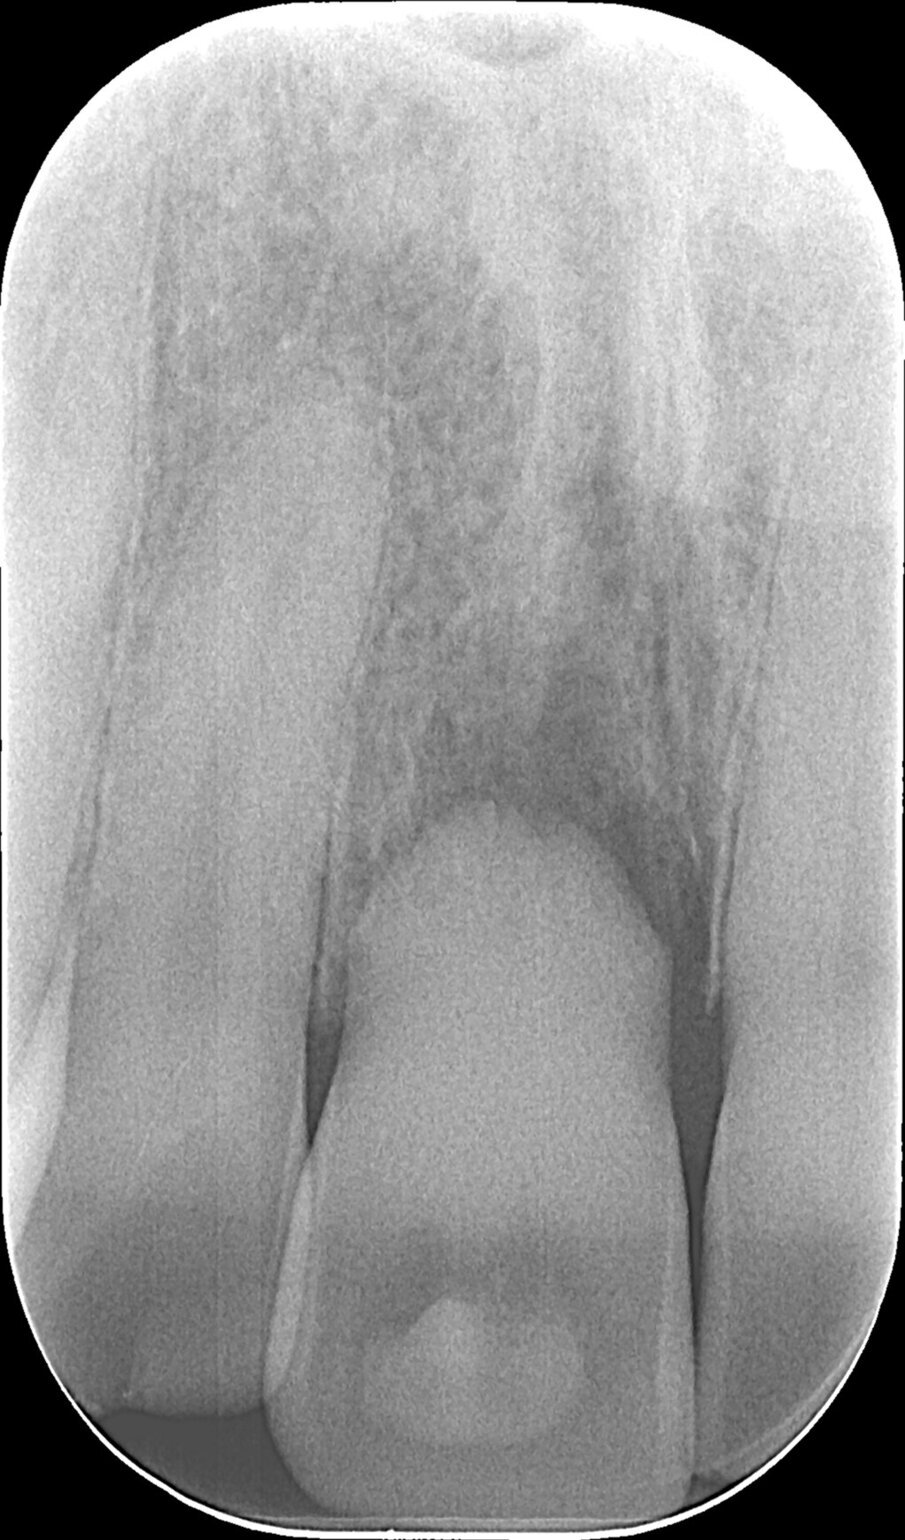

Una paziente di 34 anni di età si è presentata alla nostra osservazione lamentando la mobilità e il colore giallognolo dell’incisivo centrale superiore di destra. Effettivamente, all’esame radiografico era evidente anche un accentuato riassorbimento della radice e si decise così di programmare un impianto post-estrattivo immediato con contestuale inserimento della corona provvisoria e gestione del gap tra le pareti ossee e l’impianto con del biomateriale e dei tessuti molli per mezzo di una membrana a matrice dermica (Figg. 1, 2).

Fig. 2 - Alla rx si evidenzia un severo riassorbimento della sua radice